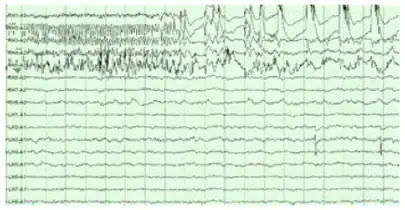

The hippocampus shows two major modes of activity, each associated with a distinct pattern of neural population activity and waves of electrical activity as measured by an electroencephalogram (EEG). These modes are named after the EEG patterns associated with them: theta and large irregular activity (LIA). The main characteristics described below are for the rat, which is the animal most extensively studied.[112]

The LIA mode appears during slow-wave sleep (non-dreaming), and also during states of waking immobility such as resting or eating.[113] In the LIA mode, the EEG is dominated by sharp waves that are randomly timed large deflections of the EEG signal lasting for 25–50 milliseconds. Sharp waves are frequently generated in sets, with sets containing up to 5 or more individual sharp waves and lasting up to 500 ms. The spiking activity of neurons within the hippocampus is highly correlated with sharp wave activity. Most neurons decrease their firing rate between sharp waves; however, during a sharp wave, there is a dramatic increase in firing rate in up to 10% of the hippocampal population.[117]

Sharp waves

During sleep or during resting, when an animal is not engaged with its surroundings, the hippocampal EEG shows a pattern of irregular slow waves, somewhat larger in amplitude than theta waves. This pattern is occasionally interrupted by large surges called sharp waves.[127] These events are associated with bursts of spike activity lasting 50 to 100 milliseconds in pyramidal cells of CA3 and CA1. They are also associated with short-lived high-frequency EEG oscillations called "ripples", with frequencies in the range 150 to 200 Hz in rats, and together they are known as sharp waves and ripples. Sharp waves are most frequent during sleep when they occur at an average rate of around 1 per second (in rats) but in a very irregular temporal pattern. Sharp waves are less frequent during inactive waking states and are usually smaller. Sharp waves have also been observed in humans and monkeys. In macaques, sharp waves are robust but do not occur as frequently as in rats.[118]

Sharp waves appear to be associated with memory.[128] Numerous later studies, have reported that when hippocampal place cells have overlapping spatial firing fields (and therefore often fire in near-simultaneity), they tend to show correlated activity during sleep following the behavioral session. This enhancement of correlation, commonly known as reactivation, has been found to occur mainly during sharp waves.[129] It has been proposed that sharp waves are, in fact, reactivations of neural activity patterns that were memorized during behavior, driven by strengthening of synaptic connections within the hippocampus.[130] This idea forms a key component of the "two-stage memory" theory,[131] advocated by Buzsáki and others, which proposes that memories are stored within the hippocampus during behavior and then later transferred to the neocortex during sleep. Sharp waves in Hebbian theory are seen as persistently repeated stimulations by presynaptic cells, of postsynaptic cells that are suggested to drive synaptic changes in the cortical targets of hippocampal output pathways.[131] Suppression of sharp waves and ripples in sleep or during immobility can interfere with memories expressed at the level of the behavior,[132][133] nonetheless, the newly formed CA1 place cell code can re-emerge even after a sleep with abolished sharp waves and ripples, in spatially non-demanding tasks.[134]

Epilepsy

The hippocampus is one of the few brain regions where new neurons are generated. This process of neurogenesis is confined to the dentate gyrus.[174] Neurogenesis can be positively affected by exercise or negatively affected by epileptic seizures.[174]

Seizures in temporal lobe epilepsy can affect the normal development of new neurons and can cause tissue damage. Hippocampal sclerosis specific to the mesial temporal lobe, is the most common type of such tissue damage.[175][176] It is not yet clear, however, whether the epilepsy is usually caused by hippocampal abnormalities or whether the hippocampus is damaged by cumulative effects of seizures.[177] However, in experimental settings where repetitive seizures are artificially induced in animals, hippocampal damage is a frequent result. This may be a consequence of the concentration of excitable glutamate receptors in the hippocampus. Hyperexcitability can lead to cytotoxicity and cell death.[158] It may also have something to do with the hippocampus being a site of continuous neurogenesis, and to abnormalities in this process.[174][158]